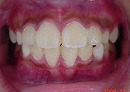

矯正前 矯正後

矯正前の写真を見ると、

上の前から2番目の歯だけ咬み合わせが上下逆になっています。

矯正後は、上下の咬み合わせが改善しています。